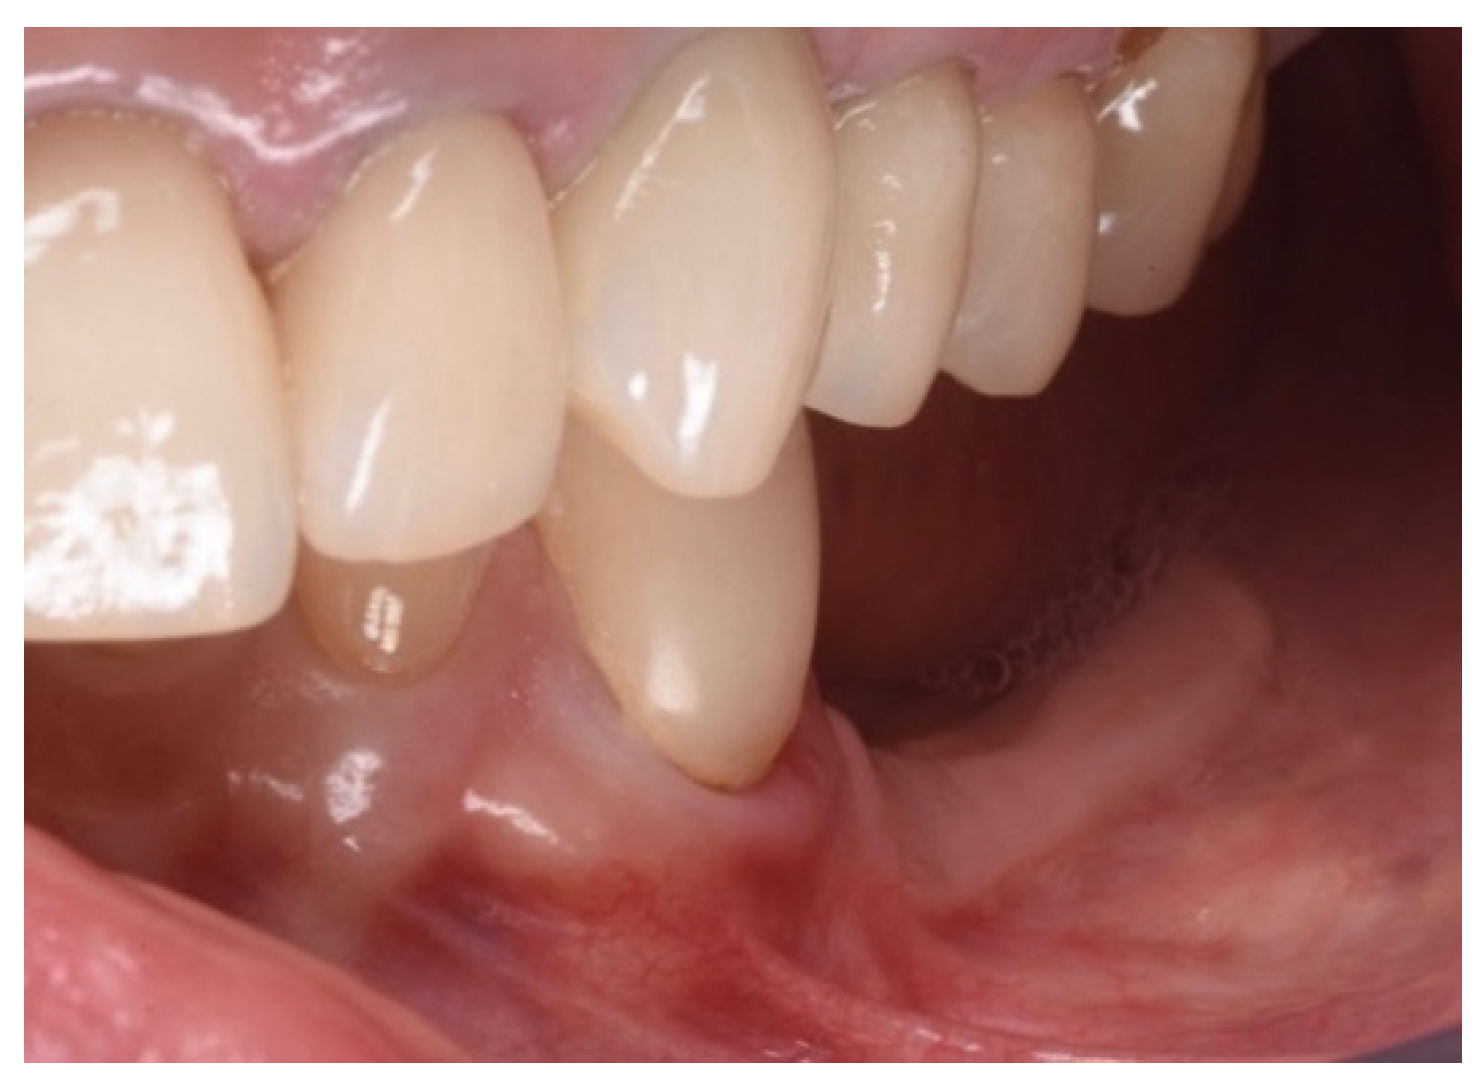

Figure 11.

Scan taken after 18 months of prosthetic loading.